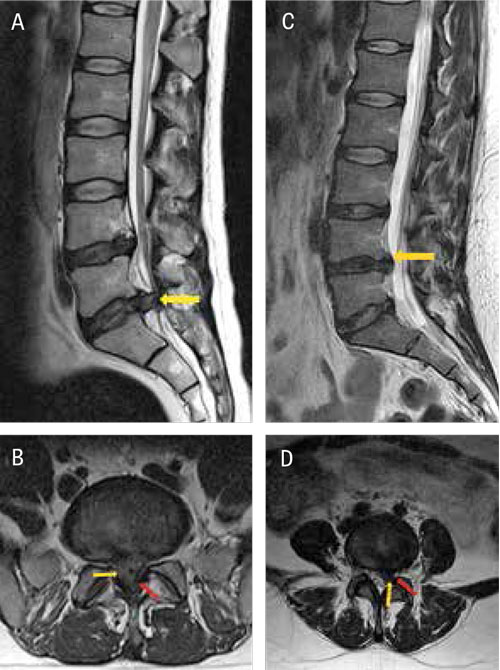

Patienter med cauda equina-syndrom på L 5–S 1-nivå i A) sagittal- och B) axialplan respektive typiskt diskbråck på L 4–L 5-nivå i C) sagittal- och D) axialplan. Diskutbuktningarna har markerats med gula pilar, medan durasäcken (B) respektive nerv­roten (D) markerats med röda pilar.